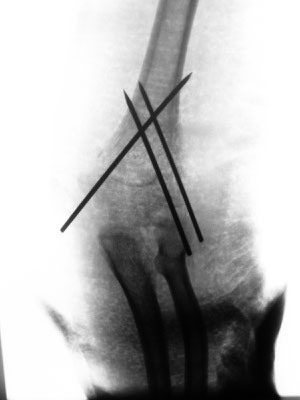

13-jähriger Junge mit Oberarmkopfbruch (Abb.1). Nicht operative Behandlung. Abb.2 zeigt das Röntgenbild nach 1 Jahr. Abb.3 zeigt die Funktion nur 2 Monaten nach dem Unfall!

8-jähriger Junge mit ellenbogennahem Oberarmbruch. Der Bruch musste operativ eingerichtet werden. Stabilisierung mit Drähten, Gips für 3 Wochen. Die Drähte werden nach 3 Monaten wieder entfernt.